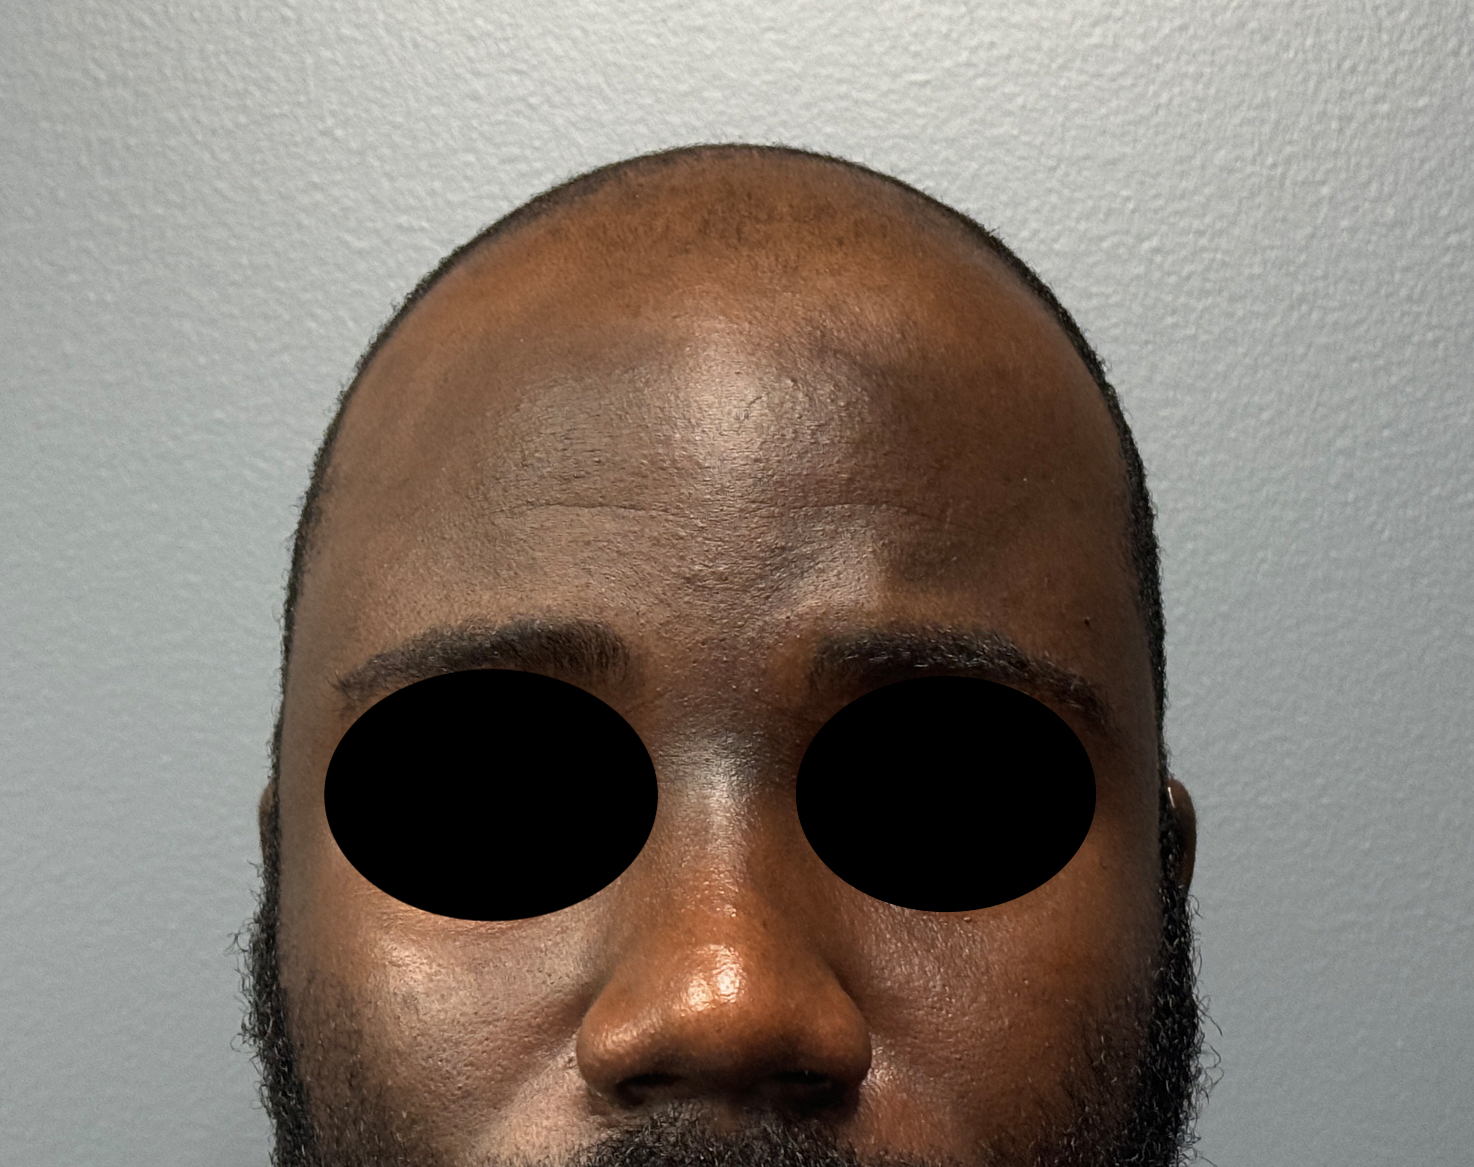

Patient 51

Desire for improved head shape that has a less peaked shape.

Placement of custom skull implant.

Desire for improved head shape that has a less peaked shape.

Placement of custom skull implant.